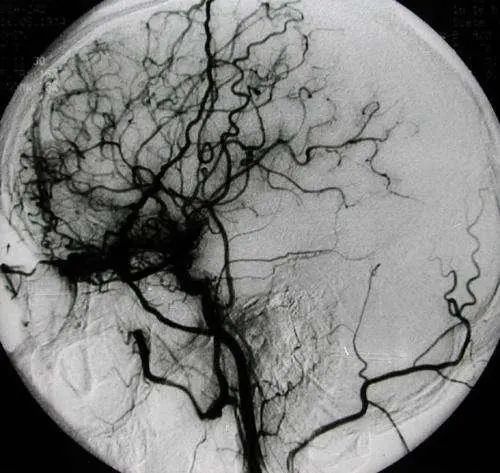

烟雾病是一种病因不明的、以双侧颈内动脉末端及大脑前动脉、大脑中动脉起始部慢性进行性狭窄或闭塞为特征,并继发颅底异常血管网形成的一种脑血管疾病。由于这种颅底异常血管网在脑血管造影图像上形似“烟雾”,故称为“烟雾病”。